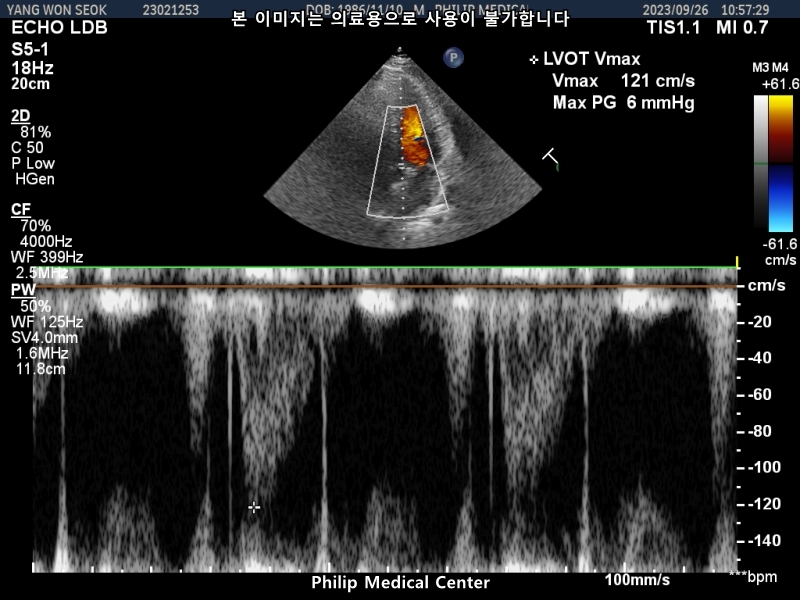

심장초음파는 경미한 폐동맥 판막역류소견과 심전도 검사결과 비특이적 ST-T파 이상소견이있었습니다.

• 4번 째 사진